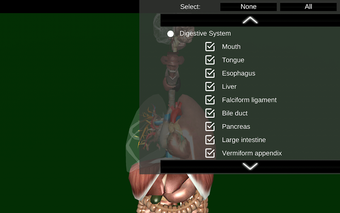

Sie können jedes Organ wie Herz, Gehirn, Lunge, Fortpflanzungssystem, Leber, Darm, Eierstock, Hoden, Magen, Niere usw. anfassen.

Sie ist für alle Menschen nützlich, auch für Studenten, da jedes Anatomieorgan in einer anderen Farbe dargestellt ist.

Sie können die App verwenden, um herauszufinden, welches die verschiedenen Körperorgane sind und welche Funktionen sie haben.